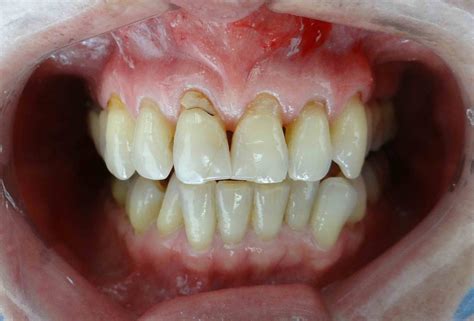

La retracción de encías sucede cuando el tejido que cubre las raíces de los dientes se desgasta o se retrae, dejando al descubierto parte del diente e incluso su raíz. La retracción gingival ocurre cuando el borde de la encía retrocede sobre la superficie de los dientes y, en consecuencia, una parte mayor queda al descubierto.

Al principio, quizá aprecies que se ven los cuellos, pero al progresar también distinguirás parte de las raíces. Por este motivo, observarás que las piezas dentales lucen más largas y la posible aparición de úlceras o aftas bucales.

- Se notan los dientes más largos: aunque parece difícil de detectar sí que es posible notar una longitud mayor de las piezas respecto a hace algún tiempo. Fíjate en tus dientes y en la posición de las encías ¿notas que ha aumentado la separación?

- Color diferente en la línea de encías: si eres un poco observador puedes detectar tonos distintos entre la raíz expuesta y la corona del diente. Si te acostumbras a fijarte en tus dientes cada vez que realizas tu rutina de limpieza, serás más consciente del estado en el que se encuentran dientes y encías y podrás comprobar si surgen cambios o algún problema.